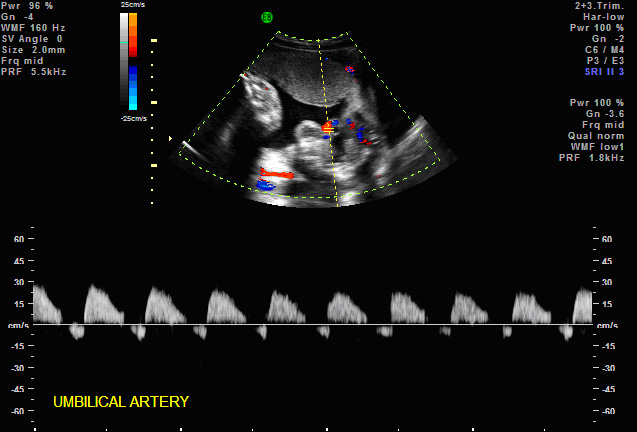

Absent umbilical artery blood

flow in severe growth delay

Reversed umbilical artery blood

2. Umbilical Arteries — contains 40% of fetal ventricular output in both arteries. Traditionally the systolic flow to diastolic flow or S/D ratio has been used to monitor fetuses at risk. The umbilical Doppler has been particularly useful in managing patients with IUGR, preeclampsia, complicated medical illnesses (diabetes, lupus, etc). (Harrington K, Carpenter RG, Nguyen M, Campbell S. Changes observed in Doppler studies of the fetal circulation in pregnancies complicated by pre-eclampsia or the delivery of a small-for-gestational baby. I. Cross-sectional analysis. Ultrasound Obstet Gynecol 1995;6:19-28. & Pattinson RC, Norman K, Odendaal HJ. The role of Doppler velocimetry in the management of high risk pregnancies. Br J Obstet Gynaecol 1994;101:114-120. & Trudinger BJ, Cook CM, Giles WB, Ng S, Fong E, Connelly A, Wilcox W. Fetal umbilical artery velocity waveforms and subsequent neonatal outcome. Br J Obstet Gynaecol 1991;98:378-84) The ranges are gestationally determined with slightly higher S/D ratios (> 2.5-4.0) in early gestations prior to 24 weeks and the lower S/D ratios ( < 3.0) greater 24 weeks. The absence of end diastolic or reversed end diastolic flow is particularly worrisome. Most believe that the absence or reversed flow in the umbilical artery S/D ratio means a very high risk of stillbirth within 48-72 hours. (Karsdorp VH, Van Vugt JM, van Geijn HP, Kostense PJ, Arduini D, Montenegro N, Todros T. Clinical significance of absent or reversed end diastolic velocity waveforms in umbilical artery. Lancet 1994;344:1664-8 & Kurkinen-Raty M, Kivela A, Jouppila P. The clinical significance of an absent end-diastolic velocity in the umbilical artery detected before the 34th week of pregnancy. Acta Obstet Gynecol Scand 1997;76:398-404)

More recently, the pulsatility index (PI) has been used since it is not affected by the reverse or absence of end-diastolic flow. Reference ranges are used for the 5th and 95th percentiles. (Harrington K, Carpenter RG, Nguyen M, Campbell S. Changes observed in Doppler studies of the fetal circulation in pregnancies complicated by pre-eclampsia or the delivery of a small-for-gestational baby. I. Cross-sectional analysis. Ultrasound Obstet Gynecol 1995;6:19-28.)